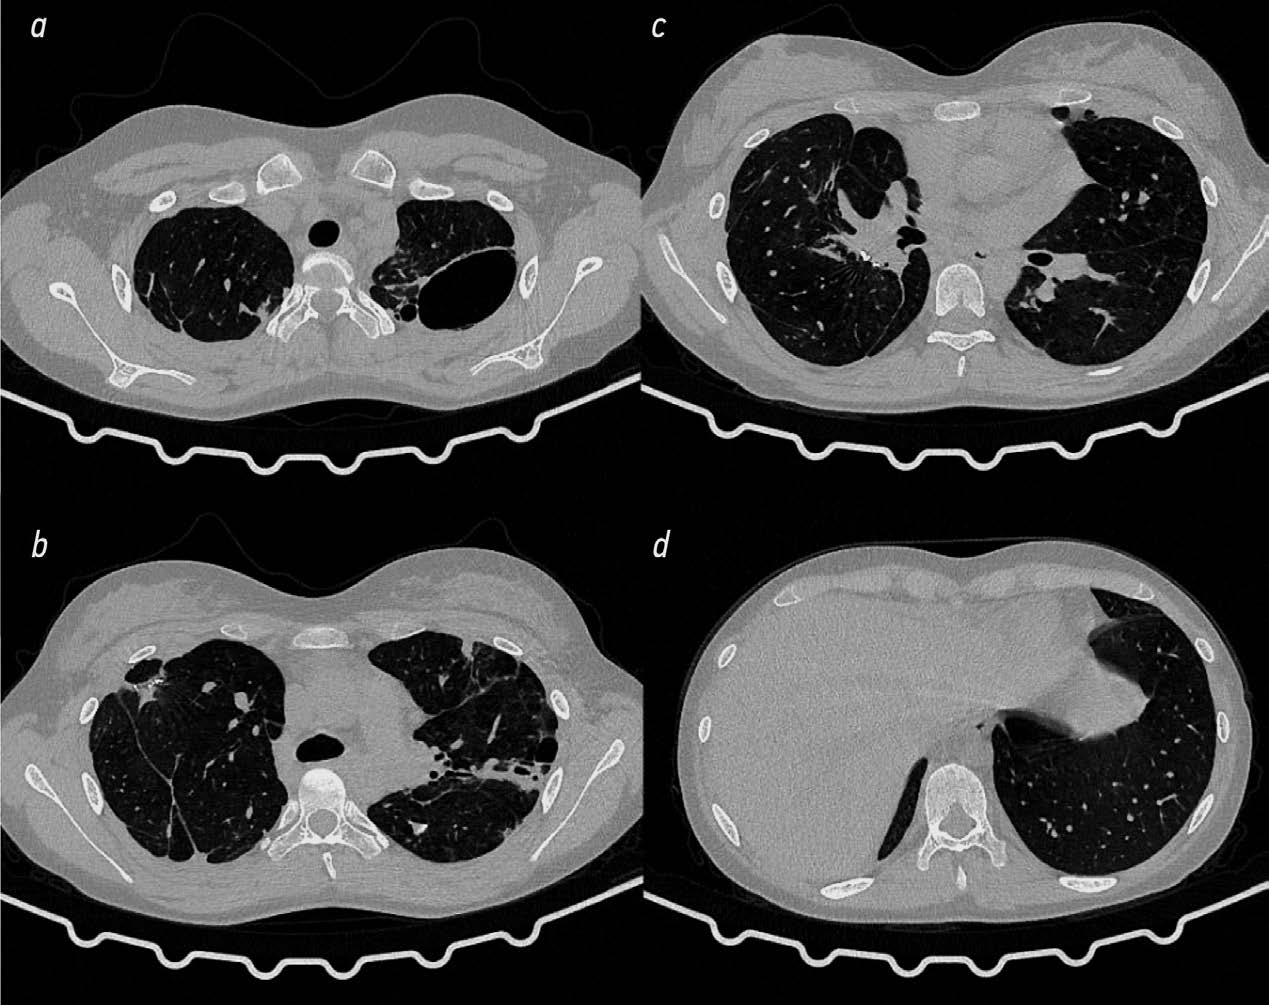

КТ ОГК через 3 мес. после 2 этапа хирургического лечения (рис. 7): состояние после верхней лобэктомии с резекцией SVI и частей SV, IX правого лёгкого, резекции SI–III с частью SVI левого лёгкого; справа видна пневматизированная зона цепочек танталовых скоб, слева — перигилярная инфильтрация; в зоне танталовых скоб определяется инфильтративно-ателектатический участок уплотнения лёгочной ткани сегментарной протяжённости.

Рис. 7. Компьютерная томография органов грудной клетки через 3 мес. после комбинированной резекции левого лёгкого (описание в тексте).

Fig. 7. Computed tomography of the chest organs 3 months after combined resection of the left lung (description in the text).